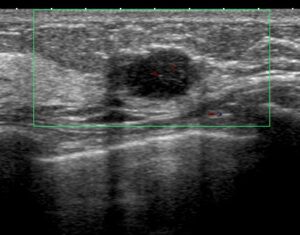

Aクリニック 初診時US ②

これを自信たっぷり「大丈夫だ、線維腺腫」っていったわけ?

このエコー見たとき、おったまげた(昭和?)よ!

とても画像だけで「線維腺腫と言い切れるレベル=きれいな楕円形」ではないよね??